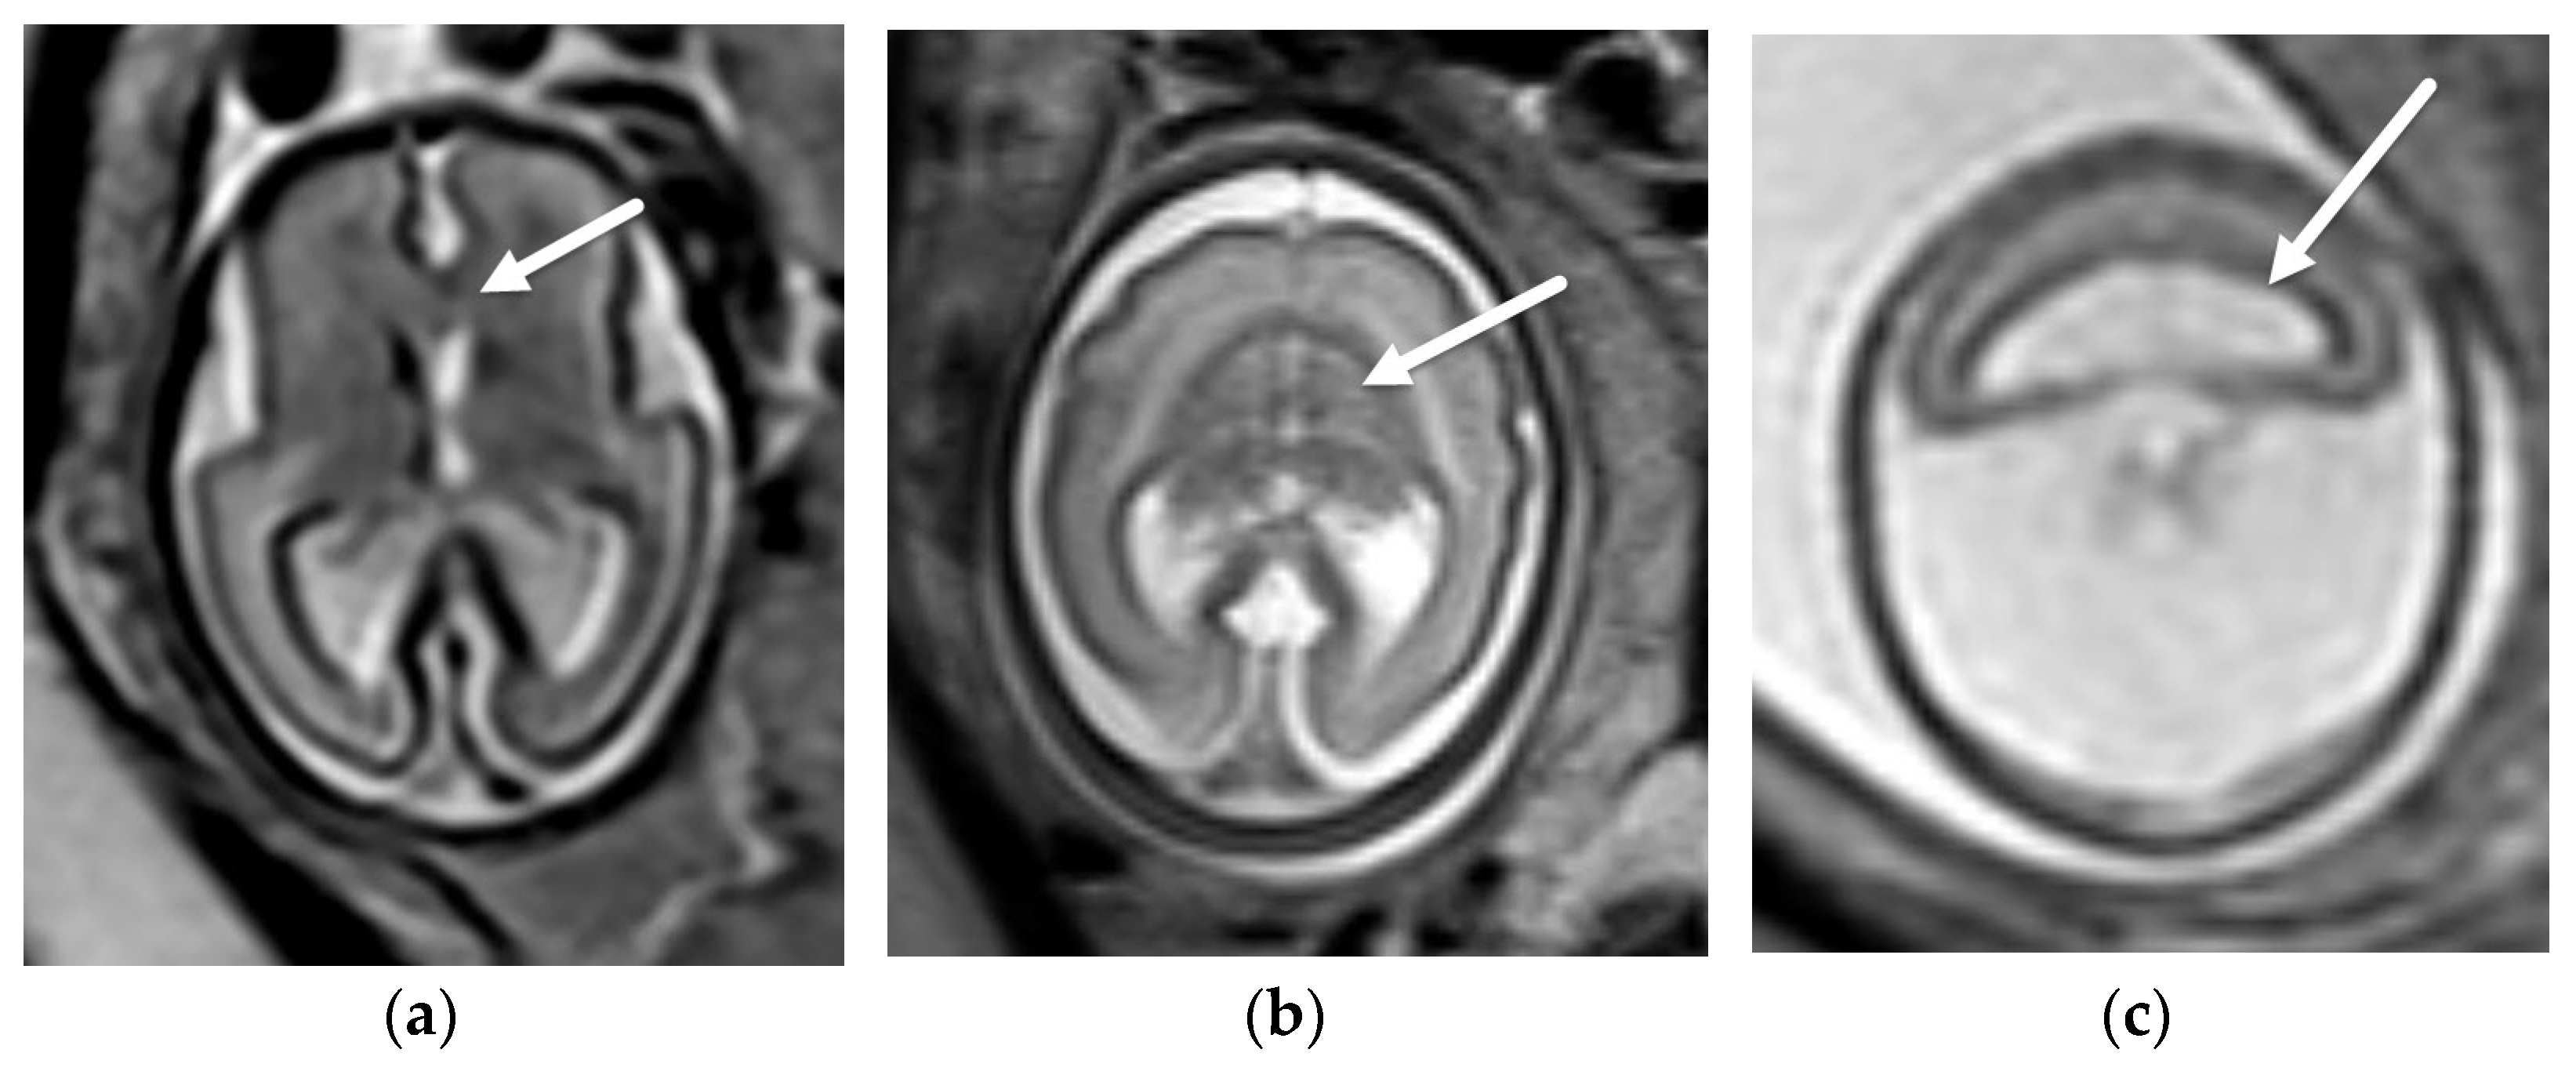

3.1.2. Chiari II Malformation

- Stevenson, K.L. Chiari Type II malformation: Past, present, and future. Neurosurg. Focus 2004, 16, 1–7. [Google Scholar] [CrossRef]

- Van den Hof, M.C.; Nicolaides, K.H.; Campbell, J.; Campbell, S. Evaluation of the lemon and banana signs in one hundred thirty fetuses with open spina bifida. Am. J. Obstet. Gynecol. 1990, 162, 322–327. [Google Scholar] [CrossRef]

- Sutton, L.N.; Adzick, N.S.; Bilaniuk, L.T.; Johnson, M.P.; Crombleholme, T.M.; Flake, A.W. Improvement in hindbrain herniation demonstrated by serial fetal magnetic resonance imaging following fetal surgery for myelomeningocele. J. Am. Med. Assoc. 1999, 282, 1826–1831. [Google Scholar] [CrossRef] [Green Version]

- Nagaraj, U.D.; Bierbrauer, K.S.; Zhang, B.; Peiro, J.L.; Kline-Fath, B.M. Hindbrain Herniation in Chiari II Malformation on Fetal and Postnatal MRI. AJNR Am. J. Neuroradiol. 2017, 38, 1031–1036. [Google Scholar] [CrossRef] [PubMed] [Green Version]